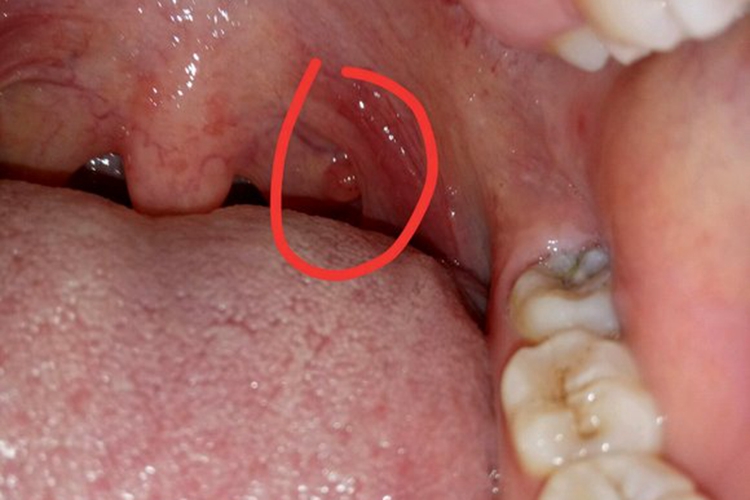

喉咙里长疣体多见腭部出现呈苍白色或肉色的乳头状、菜花状赘生物,患者多无自觉症状,该症状多见于口腔内尖锐湿疣。

口腔内尖锐湿疣初发损害为小而柔软的粉红色丘疹,一般为针帽或米粒大,逐渐增大至长锥形疣状物,可单发或数量逐渐增多,表面多高低不平,质地柔软,即喉咙里长疣体的表现。如不及时治疗,疣体将逐渐增大,成为大的菜花状或乳头瘤样。患者一般无自觉症状,可有异物感。